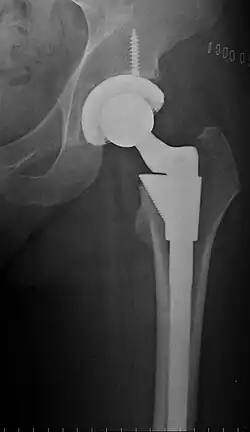

Post-operative projectional radiography is routinely performed to ensure proper configuration of hip prostheses.

The direction of the acetabular cup influences the range of motion of the leg, and also affects the risk of dislocation.[16] For this purpose, the acetabular inclination and the acetabular anteversion are measurements of cup angulation in the coronal plane and the sagittal plane, respectively.